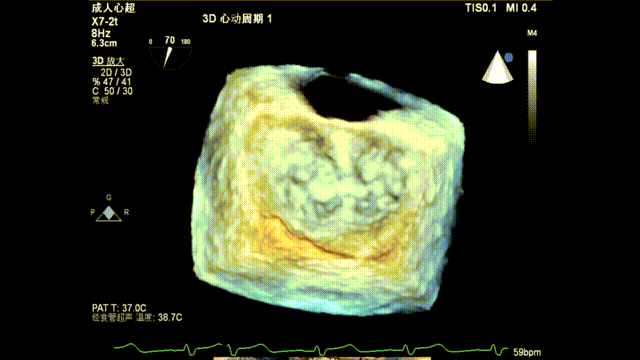

术前TEE显示重度功能性二尖瓣反流,反流位于A2/P2;

术后超声评估

术后TEE显示二尖瓣双孔化形成,反流明显减少,瓣膜夹位置稳定,二尖瓣跨瓣平均压力阶差为4mmHg,植入后反流下降至1+